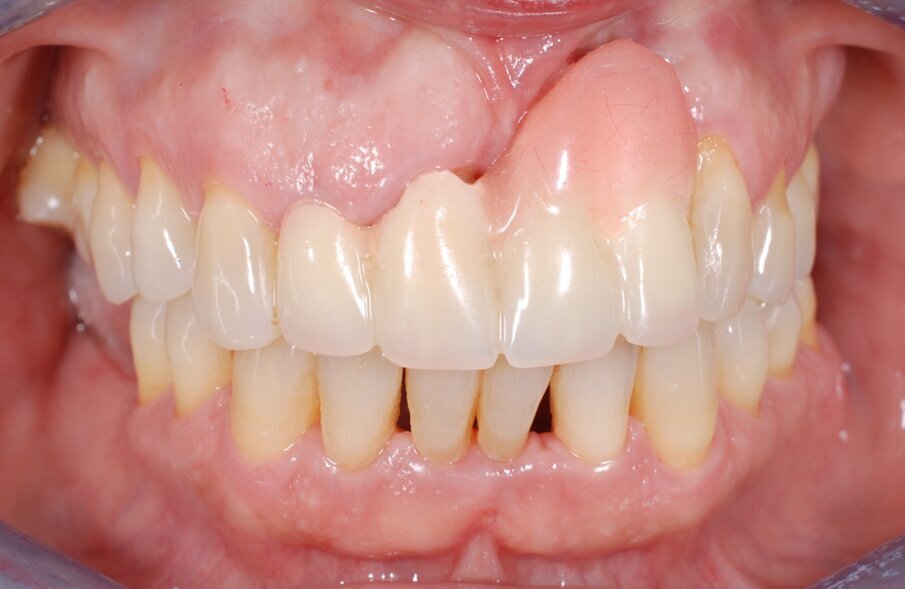

In questo articolo presentiamo un caso clinico che dimostra come il posizionamento improprio di un impianto può rendere impossibile la riabilitazione protesica, che richiede una nuova pianificazione chirurgica e riabilitativa per ottenere l’estetica desiderata. La paziente si presenta alla nostra osservazione con una riabilitazione protesica incongrua, con flangia in resina, a supporto dentale ed implantare, con la presenza di un impianto in posizione 2.1 vestibolarizzato e con l’emergenza nel fornice, in mucosa alveolare. Dalla valutazione della Tac si evince la posizione errata dell’impianto e la perdita consistente in senso trasversale della compagine ossea (Figg. 1, 2). Pertanto si opta per il seguente piano di trattamento che prevede: rimozione dell’impianto e preparazione protesica dell’elemento 2.3, confezionamento di un primo provvisorio a supporto dentale che servirà a guidare la guarigione dei tessuti (Figg. 3-7). A distanza di 4 mesi si procede a un innesto epitelio connettivale libero con prelievo dal palato per compensare il gap dei tessuti molli in senso trasversale, quindi viene ribasato il provvisorio in modo tale da favorire la guarigione dei tessuti (Figg. 8-11). A 9 mesi dalla maturazione dei tessuti si procede alla finalizzazione protesica fissa a supporto dentale (Figg. 12-14).

Fig. 7 - Applicazione del provvisorio dopo preparazione protesica del 2.3 e frenulectomia laser.